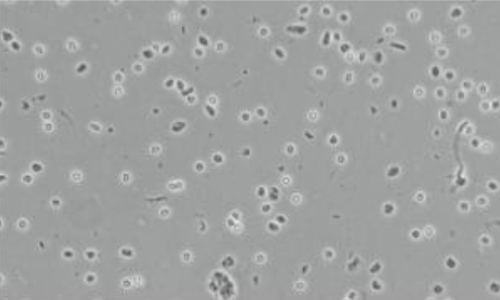

本产品专为从人、小鼠等动物 FFPE 样本中分离高纯度的单细胞核而设计。组织经过脱蜡、水化、细胞膜裂解等步骤释放完整细胞核,同时维持核膜稳定性,过滤和清洗环节可进一步去除细胞碎片和杂质,从而满足下游单细胞组学、表观遗传学等前沿研究领域对细胞核的质量要求。本产品广泛适用于各种组织类型,全流程操作简捷,为复杂样本提供标准化的解决方案。

·可在 1.5 小时内完成 2 - 4 个 FFPE 样本的细胞核分离,操作简单,方便快捷,获得的细胞核形态较好,背景干净。

▲人食管癌 FFPE 样本 |

▲人胶质瘤 FFPE 样本 |

▲人肺 FFPE 样本 |

▲人肝脏 FFPE 样本 |

▲人前列腺 FFPE 样本 |

▲小鼠 FFPE 样本 |

伯优 ®FFPE 样本细胞核分离试剂盒,已用于多种哺乳动物 FFPE 组织的细胞核提取,如 小鼠肝、肾、脑,人肝、淋巴、宫颈 等。